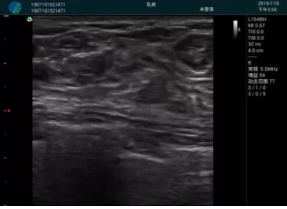

清晰顯示腺體內(nèi)低回聲快影,邊界清晰,包膜較光滑

確定進(jìn)針路徑并實(shí)時(shí)監(jiān)測(cè)抽吸針與腫塊位置關(guān)系

抽吸針進(jìn)入腫塊內(nèi)部進(jìn)行旋切

抽吸過(guò)程中可見(jiàn)腫塊明顯縮小,并根據(jù)腫塊位置改變針道位置

抽吸旋切后再進(jìn)行超聲復(fù)查,原腫塊區(qū)域未見(jiàn)殘留組織及出血